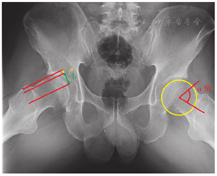

此外,骨盆正位X线片中常用来测量的指标有股骨头突出指数(femoral head extrusion index)、股骨颈干角(femoral neck-shaft,FNS)、髋臼深宽比(acetabulardepth-to-width ratio)、LCEA、Tönnis角和Sharp角。股骨头突出指数是指股骨头超出髋臼以外部分的横径与股骨头直径的比值,正常值为25%,突出指数过大则提示髋臼发育不良[33]。股骨颈干角是股骨干与股骨颈轴线的夹角,平均约127°,<120°为髋内翻、>140°为髋外翻(若伴有髋关节发育不良则容易发生髋关节脱位,髋关节镜手术的结局可能不良)[34]。髋臼上下缘之间的距离为髋臼宽度,髋臼最深点与髋臼上下缘连线之间的垂直距离为髋臼深度,深度与宽度之比正常应>38%,若偏小则提示可能存在髋关节发育不良[33]。LCEA是经过股骨头中心的垂线与股骨头中心和髋臼外上缘连线的夹角,能够反映股骨上外侧方向的髋臼覆盖,正常值为25°~40°,LCEA<25°常提示髋臼覆盖不足,为髋臼发育不良的重要影像学特点,>40°时提示髋臼过度覆盖,是Pincer型FAI的一个合理的评估指标[35,36,37]。LCEA除辅助诊断FAI外,还是髋关节镜下骨软骨成形术治疗FAI的术后评价指标,并用于预测术后结果,较大的LCEA常预示着不良预后。为保证术后病情改善,推荐将LCEA纠正至30°[38,39]。FAI同样可合并髋臼发育不良,一项5年随访研究证实合并髋臼发育不良的FAI者可通过髋关节镜手术获得与正常髋关节覆盖的FAI患者相似的改善[40]。Tönnis角是通过髋臼负重区内侧外侧点的切线,与平行于骨盆横轴的水平线之间的夹角,正常范围为0°~10°,<0°提示髋关节可能存在髋臼过度覆盖及Pincer型撞击,>10°提示髋臼覆盖不足,可能存在髋臼发育不良的情况[41,42]。Sharp角常用于评估髋关节发育程度,测量方法是髋臼泪滴远端和髋臼最外缘点的连线与骨盆水平线之间的夹角,Sharp角≥45°表示髋臼顶对股骨头的覆盖不足,提示髋关节发育不良[42]。

假斜位X线片最常用的指标是前中心边缘角(anterior center-edge angle,ACEA)。ACEA由Lequesne等[44]提出,是经过股骨头中心的垂线与股骨头中心和髋臼前缘连线所形成的夹角,可反映髋臼前方覆盖的程度(图3)。ACEA是诊断髋臼发育不良、Pincer型髋臼等髋关节异常的重要考虑因素,通常ACEA<20°被视为髋臼前方覆盖不足、20°~25°被视为临界、25°~40°为正常、>40°为髋臼前方过度覆盖[45]。ACEA的准确测量受标准假斜位X线片拍摄方法和测量误差的影响。临床实践中难以严格按照标准体位拍摄假斜位片,而患者体位的改变会导致ACEA测量值的改变,标准假斜位X线片中两侧股骨头中心的距离应该约为骨盆正位X线片中距离的0.5倍,或两侧股骨头间隙为图像中股骨头直径的66%~100%[46,47,48]。测量方面误差的主要来源于髋臼前缘测量点的选取。既往研究将髋臼最前方的骨质作为髋臼前缘的测量点[44],该测量方式简便易行,但由于髂前下棘可致测量角度偏大,髋臼覆盖率较实际更高;若选取髋臼眉弓作为髋臼前缘点,可能测量的ACEA更接近实际,但由于眉弓在X线片上不一定能被清晰辨认,可能会造成测量不便甚至误差[49,50]。Sakai等[50]认为在正常髋关节中,前种测量方式能更准确地反映髋臼前覆盖,而在发育不良的髋关节中该测量方式往往会高估髋臼前覆盖的程度。